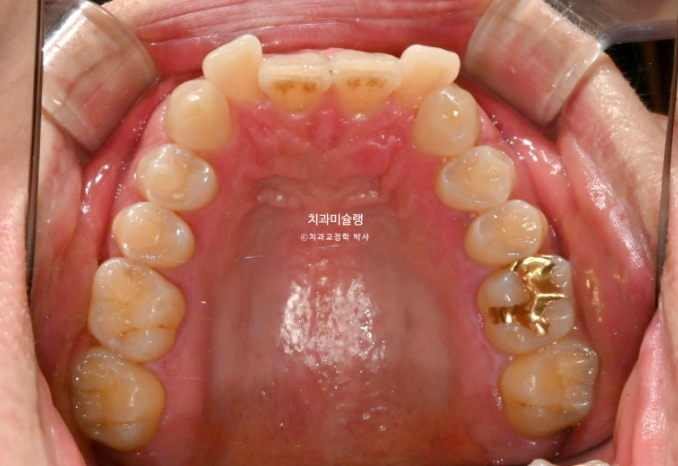

앞니 높낮이가 맞아지면 들쑥날쑥 했던 잇몸라인은 자연스럽게 맞아집니다.

앞니만 교정하는 부분교정이기에 어금니 교합은 그대로 유지됩니다.

이제 전후 비교 보겠습니다.

총 치료기간은 6개월 입니다.

25.04~25.10

중심선 불일치는 부분교정의 한계점으로 그대로 덧니를 포함한 배열만은 완벽합니다.

특히 아래 앞니 중 튀어나와있던 파란 화살표 앞니는 배열 과정에서 잇몸라인도 자연스럽게 주변과 맞아집니다.